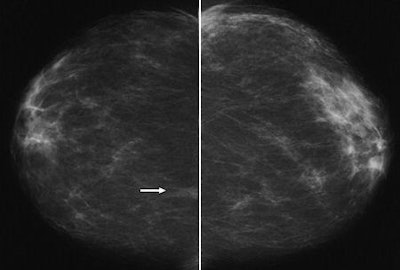

| The following images are of a 46-year-old woman with one-view asymmetry in right breast. Above, craniocaudal projection mammogram of both breasts shows one-view asymmetry (arrow) in medial aspect of right breast. All images courtesy of the American Roentgen Ray Society. |